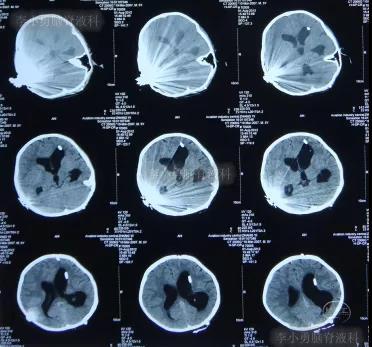

但是在住院第19天即在2012年6月6日时(注:即在人工耳蜗植入术颅内感染并发症21天时),患儿出现了左眼闭合和右侧肢体瘫痪即交叉性偏瘫,以及进食无力和不能交流的病情加重的表现,立即脑CT检查发现了脑积水的表现(图-6)。

图-6:2012年6月6日脑CT脑室扩大显著

此时,患儿的父亲感到了问题严重性,认为儿子病情已经超出了感染科的范围,所以当晚在网上查找治疗脑积水和颅内感染的相关内容,查找到了李小勇脑脊液科,经咨询后次日下午转住入李小勇脑脊液科。